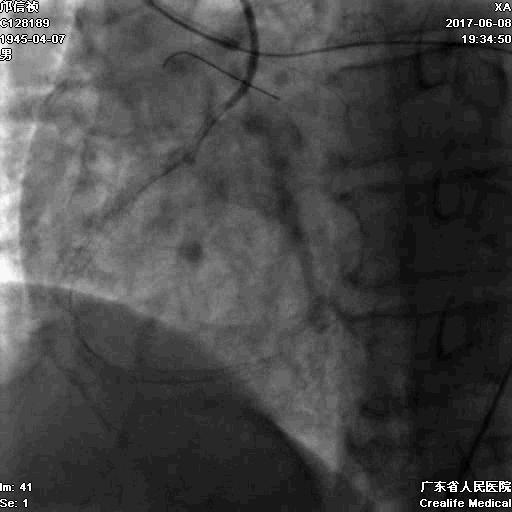

RRA:6F AL0.75 GC –RCA;

RFA:7F XB 3.5 GC—LCA 150cmcorsair

正向130cmFinecross微导管支持下尝试送PILOT150、Gaia 2导丝无法通过RCA闭塞段

SION导丝通过侧枝

逆向导丝:更换Gaia2

正向导丝:Gaia2,PILT150

正向导丝knuckle

2.5*15mm球囊扩张,逆向导丝尝试,但未能进入正向GC

1.正向2.5*15mm球囊扩张,Reverse CART

2.Guidezilla延长导管辅助下,逆向导丝进入正向GC

1.更换RG3导丝

2.GC送入普通导丝,保护LM

支架术后造影结果